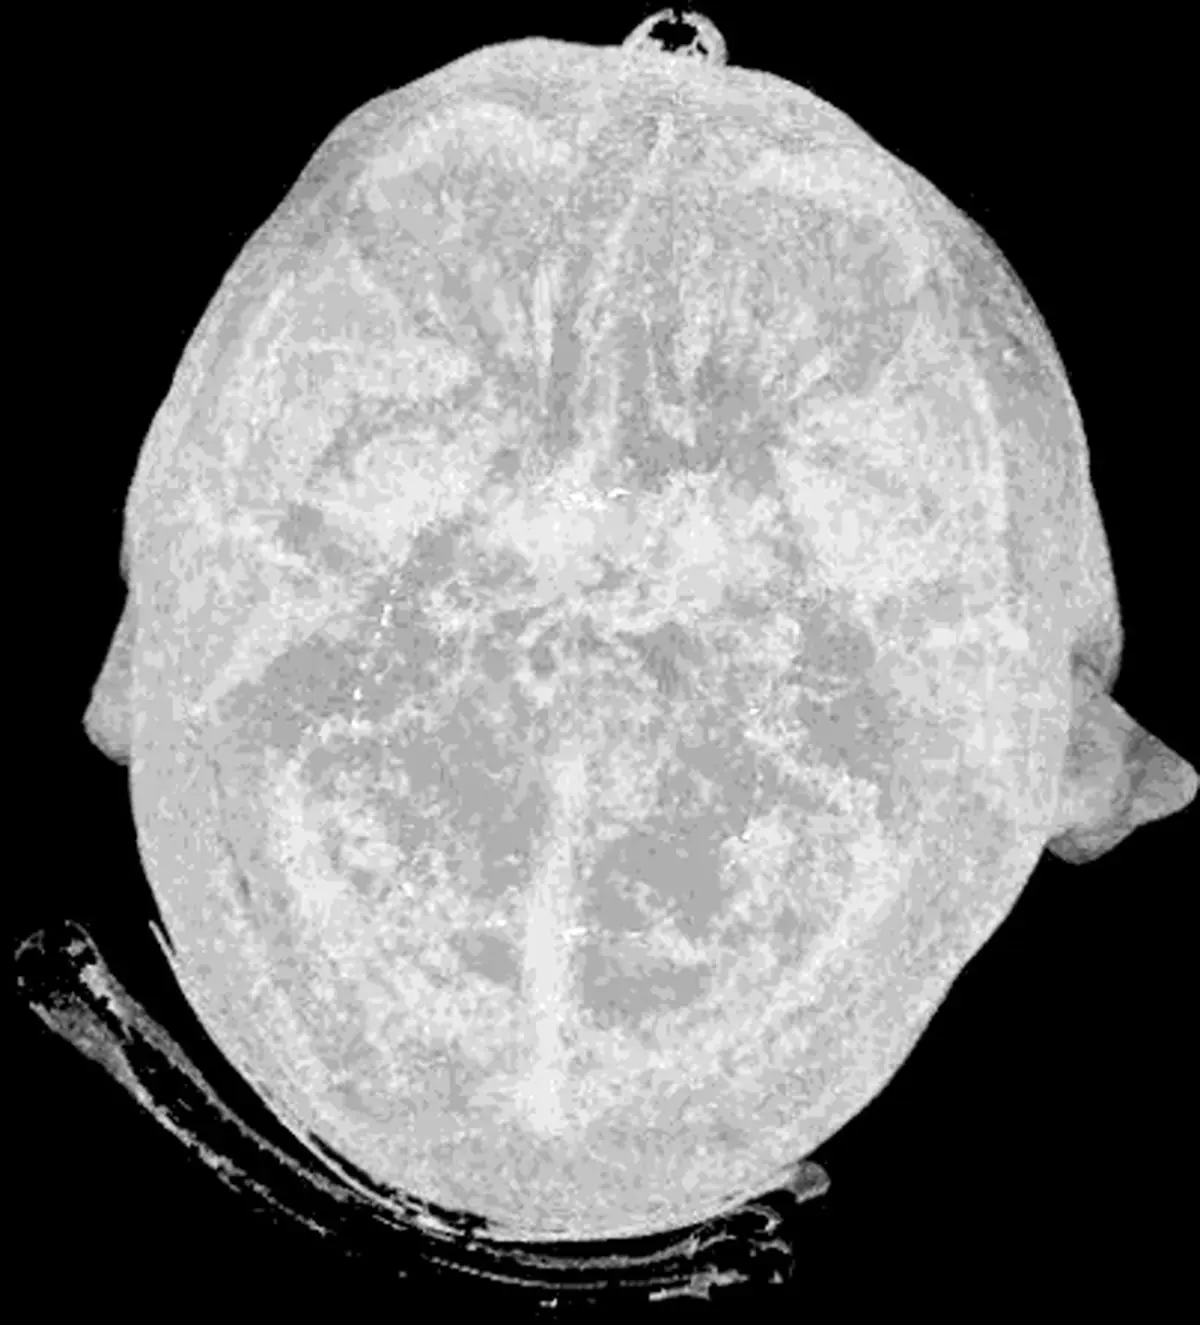

۱- مغز انسان بزرگ ترین فلش درایو دنیا است

10 حقیقت عجیب و جالب درباره بدن انسان که شگفت زده تان می‌کند!+ تصاویر

حافظه ی انسان به اندازه ی ذخیره ی ۲/۵ میلیون گیگابایت اطلاعات گنجایش دارد. این مقدار تقریباً معادل ۳۰۰ سال ویدئوی ضبط شده است. روند رشد حافظه در ۲۵ سالگی به اوج خود می رسد و از سن ۵۰ سالگی کاهش پیدا می کند، مگر آنکه حافظه ی خود را پرورش دهید.